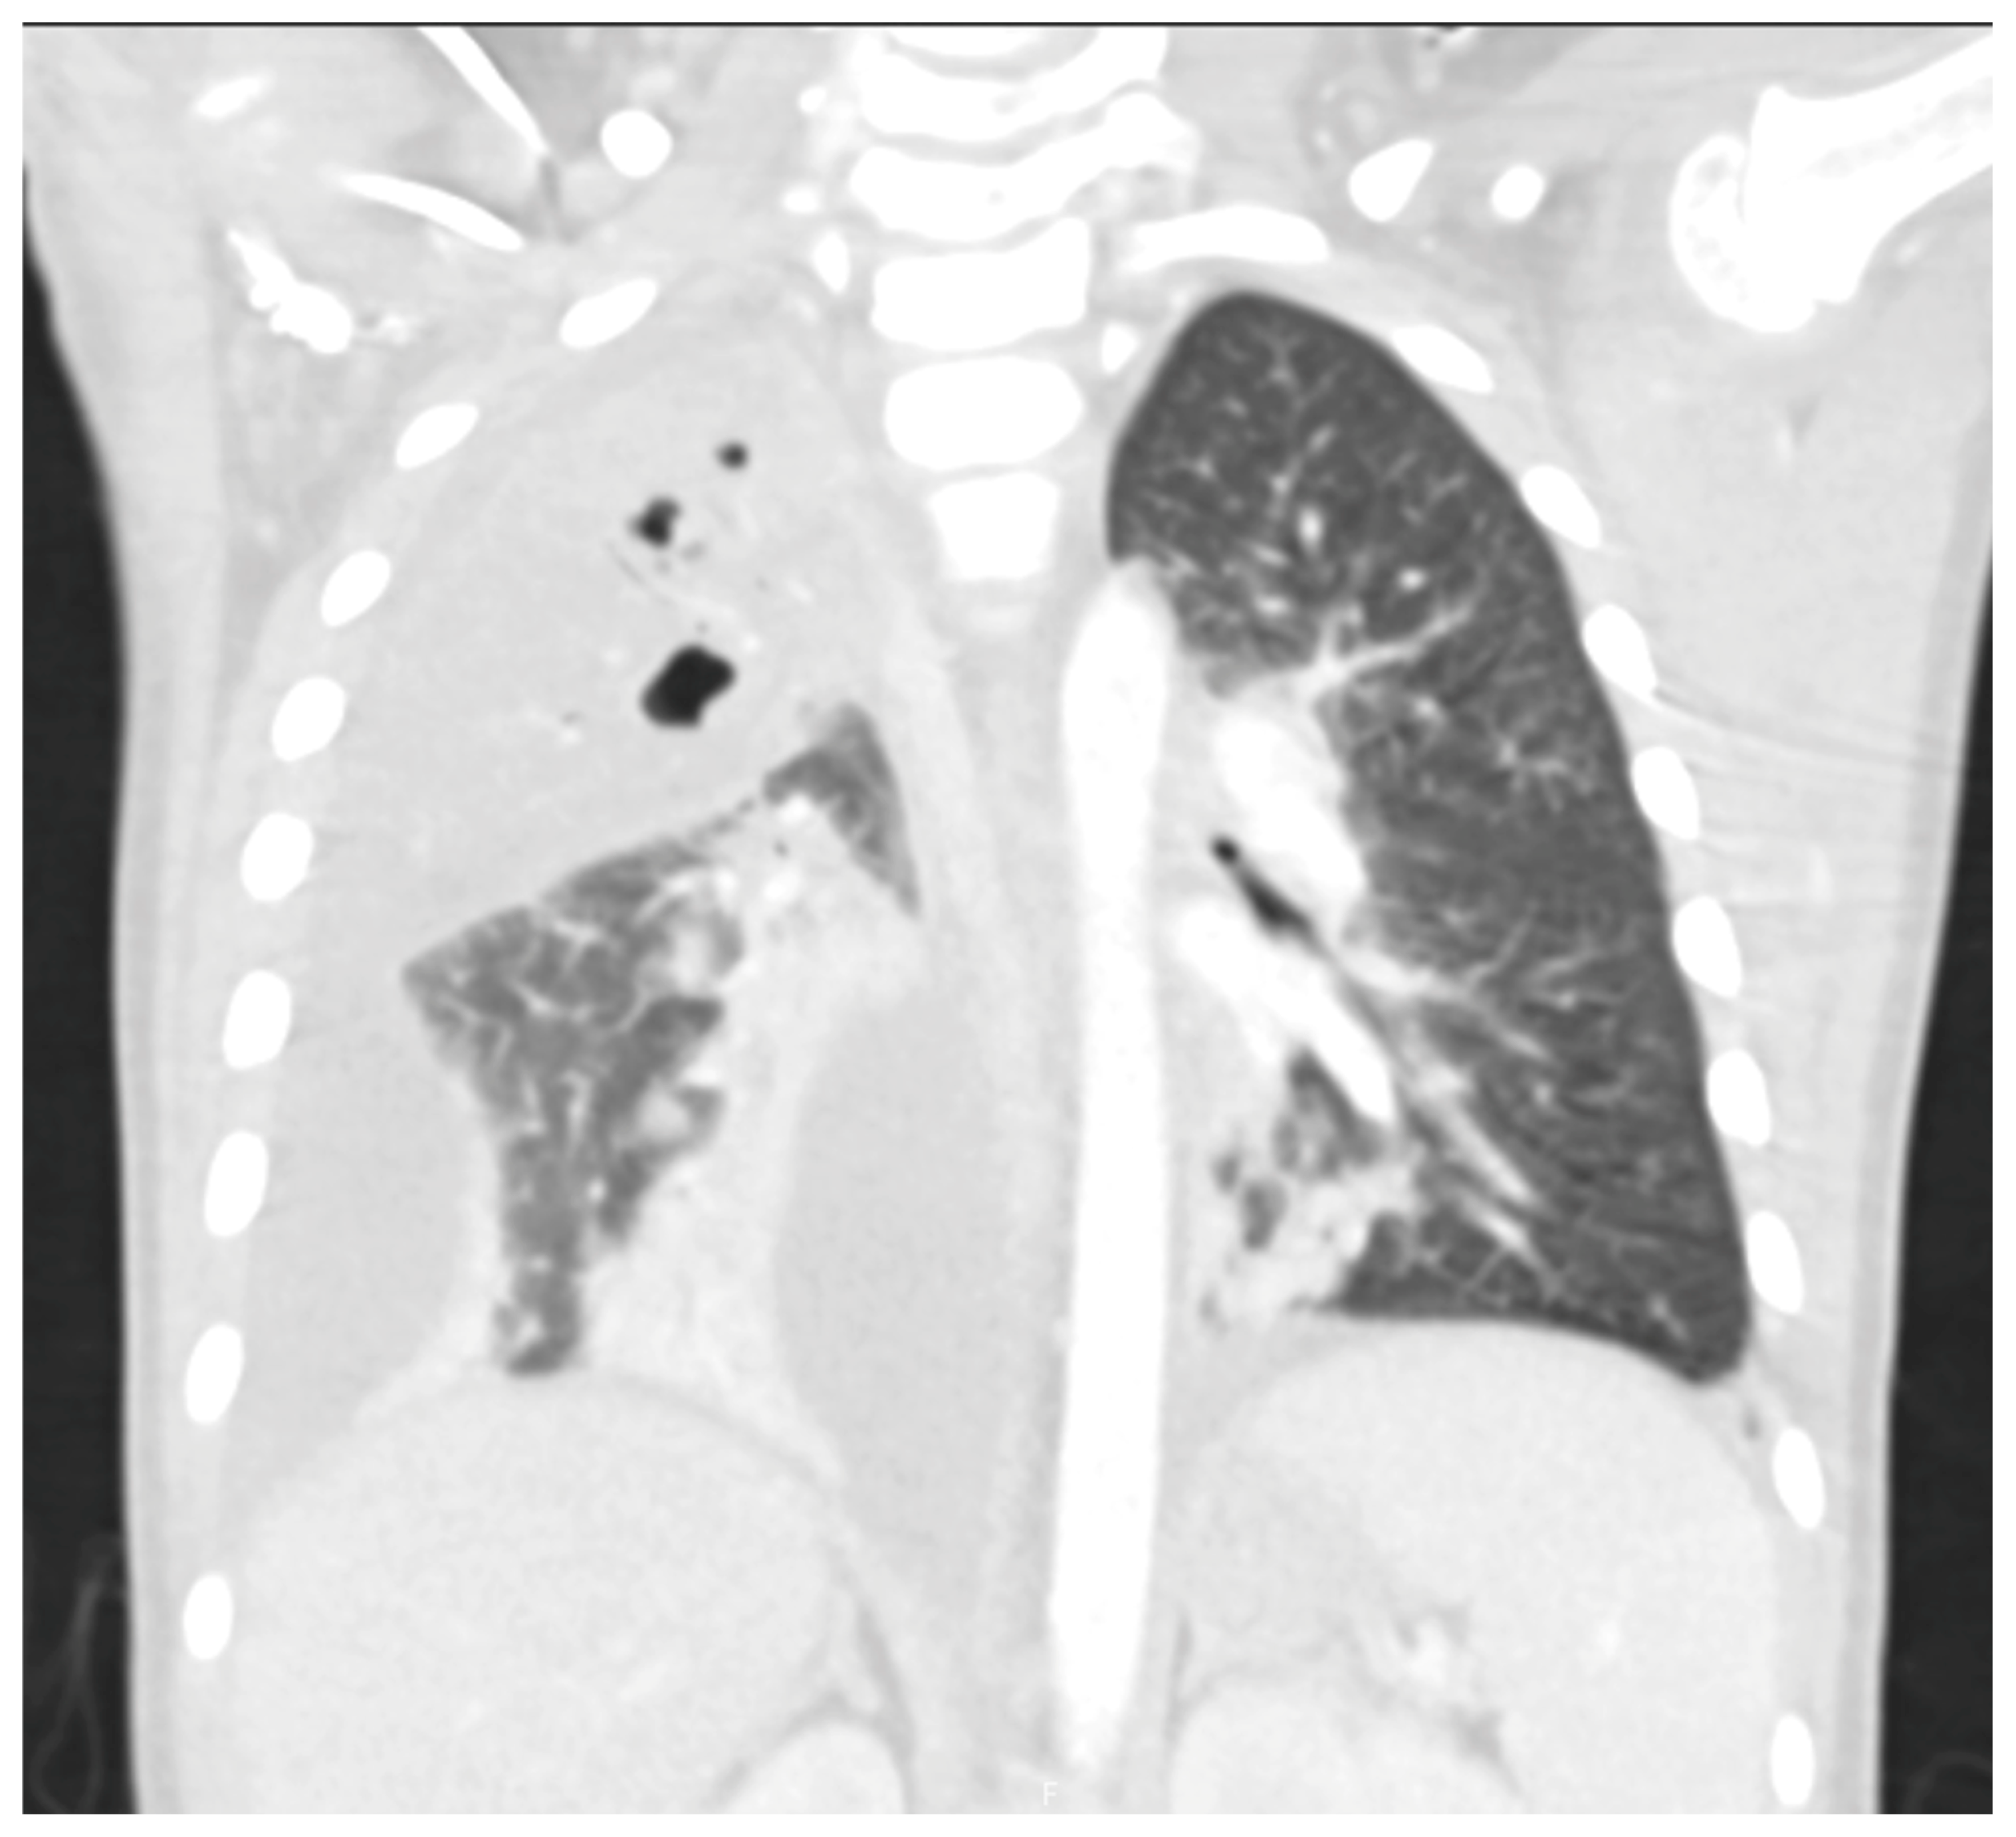

- Huang, W.E.; Matifoll, J.A.; Lord, D.; Haggie, S. A review of imaging in the diagnosis and management of complicated paediatric pneumonia. Paediatr. Respir. Rev. 2025, 54, 12–18. [Google Scholar] [CrossRef]

- Hoffer, F.; Bloom, D.; Colin, A.A.; Fishman, S.J. Lung abscess versus necrotizing pneumonia: Implications for interventional therapy. Pediatr. Radiol. 1999, 29, 87–91. [Google Scholar] [CrossRef]

- Hacimustafaoglu, M.; Celebi, S.; Sarimehmet, H.; Gurpinar, A.; Ercan, I. Necrotizing pneumonia in children. Acta Paediatr. 2004, 93, 1172–1177. [Google Scholar] [CrossRef]

- Tan Kendrick, A.P.; Ling, H.; Subramaniam, R.; Joseph, V.T. The value of early CT in complicated childhood pneumonia. Pediatr. Radiol. 2002, 32, 16–21. [Google Scholar] [CrossRef]

- Hodina, M.; Hanquinet, S.; Cotting, J.; Schnyder, P.; Gudinchet, F. Imaging of cavitary necrosis in complicated childhood pneumonia. Eur. Radiol. 2002, 12, 391–396. [Google Scholar] [CrossRef][Green Version]

- Carrard, J.; Bacher, S.; Rochat-Guignard, I.; Knebel, J.-F.; Alamo, L.; Meuwly, J.-Y.; Tenisch, E. Necrotizing pneumonia in children: Chest computed tomography vs. lung ultrasound. Front. Pediatr. 2022, 10, 898402. [Google Scholar] [CrossRef]

- Kurian, J.; Levin, T.L.; Han, B.K.; Taragin, B.H.; Weinstein, S. Comparison of ultrasound and CT in the evaluation of pneumonia complicated by parapneumonic effusion in children. Am. J. Roentgenol. 2009, 193, 1648–1654. [Google Scholar] [CrossRef] [PubMed]

- Lai, S.-H.; Wong, K.-S.; Liao, S.-L. Value of lung ultrasonography in the diagnosis and outcome prediction of pediatric community-acquired pneumonia with necrotizing change. PLoS ONE 2015, 10, e0130082. [Google Scholar] [CrossRef]